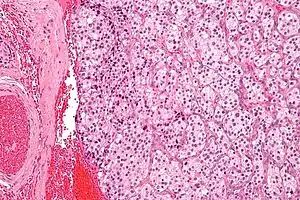

Section of part of human carotid body. Highly magnified. Numerous blood vessels are seen in section among the cells. | |

The carotid body is made up of two types of cells, called glomus cells: glomus type I cells are peripheral chemoreceptors, and glomus type II cells are sustentacular supportive cells.

- Glomus type I cells are derived from the neural crest.[4] They release a variety of neurotransmitters, including acetylcholine, ATP, and dopamine that trigger EPSPs in synapsed neurons leading to the respiratory center. They are innervated by axons of the glossopharyngeal nerve which collectively are called the carotid sinus nerve.

- Glomus type II cells resemble glial cells, express the glial marker S100 and act as supporting cells.